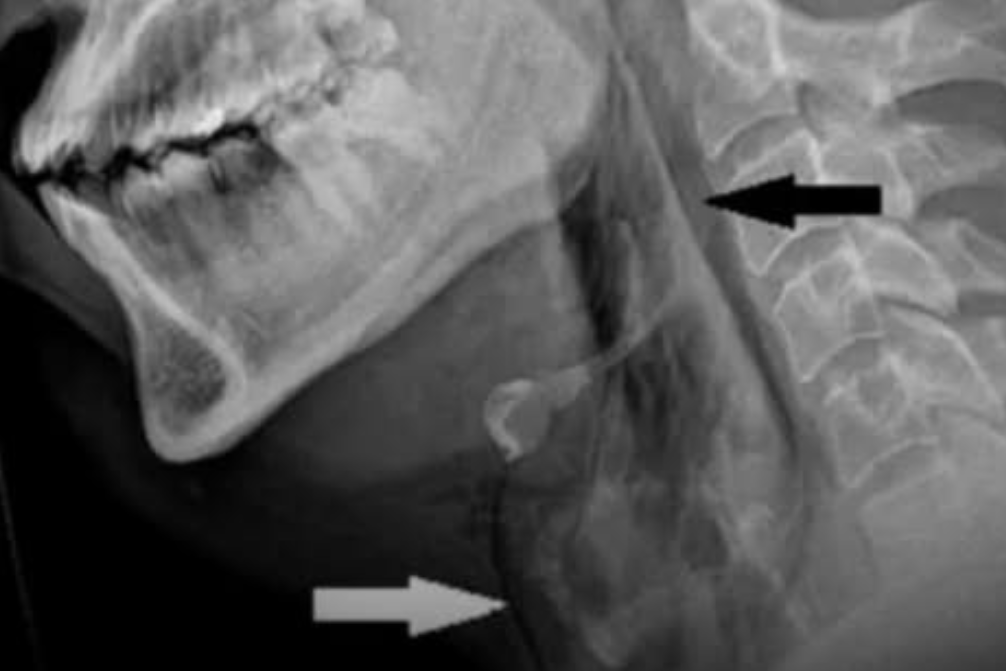

Todo sucedió mientras el paciente manejaba y trató de evitar estornudar cerrando nariz y boca. Inmediatamente sintió un dolor punzante en el cuello y buscó ayuda en el hospital Ninewells en Dundee. Los médicos notaron crujidos bajo la piel y un movimiento anormal en la tráquea.

Tras realizarle estudios de imagen, se reveló una perforación traqueal espontánea, algo extremadamente raro que normalmente solo se ve tras traumatismos fuertes o procedimientos quirúrgicos. El caso fue documentado en la revista médica BMJ Case Reports.